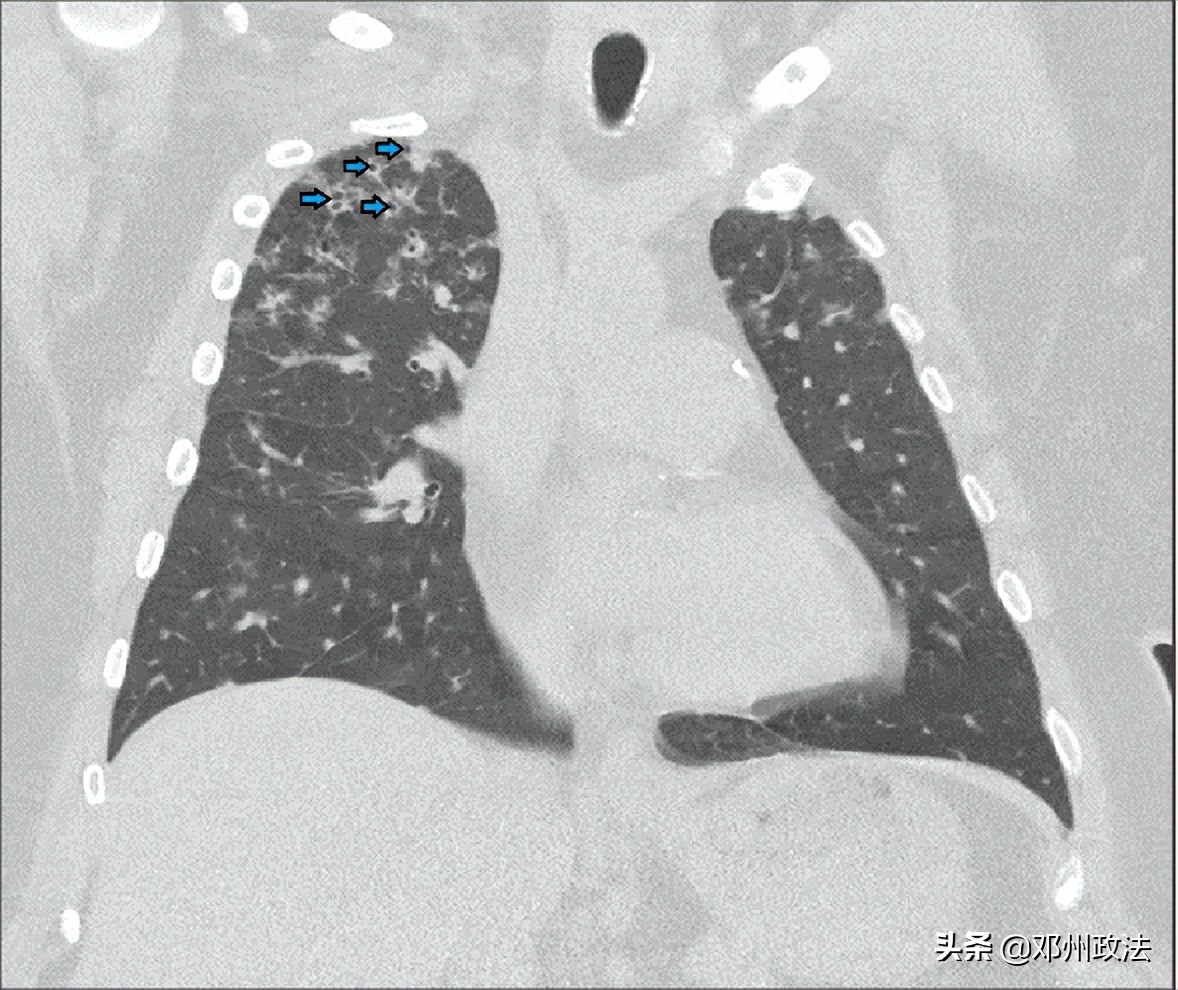

热水浴肺病的病程发展通常是亚急性的,常见症状包括呼吸困难、咳嗽、发热等,少数人会像出现较为严重的低氧血症甚至呼吸衰竭。胸部 X 光片有时会发现异常,例如肺野中弥漫性结节;高分辨率 CT 胸部扫描中常出现磨玻璃渗出以及马赛克征,也有个案报道 CT 上呈空洞性结节性病变。肺功能检查往往有混合性通气功能障碍。

非典型的热水浴肺病 CT 图像:小的空洞结节性病变(箭头)(图源:参考文献)